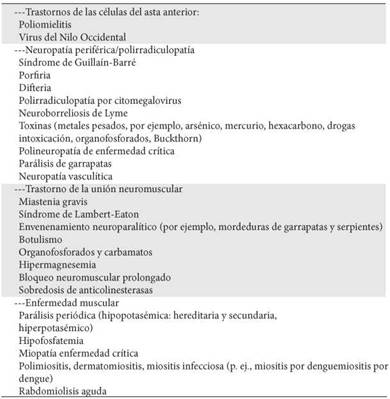

Tabla 1. Diagnóstico diferencial de la parálisis aguda neuromuscular

Adaptado de las referencias 1 y 2.